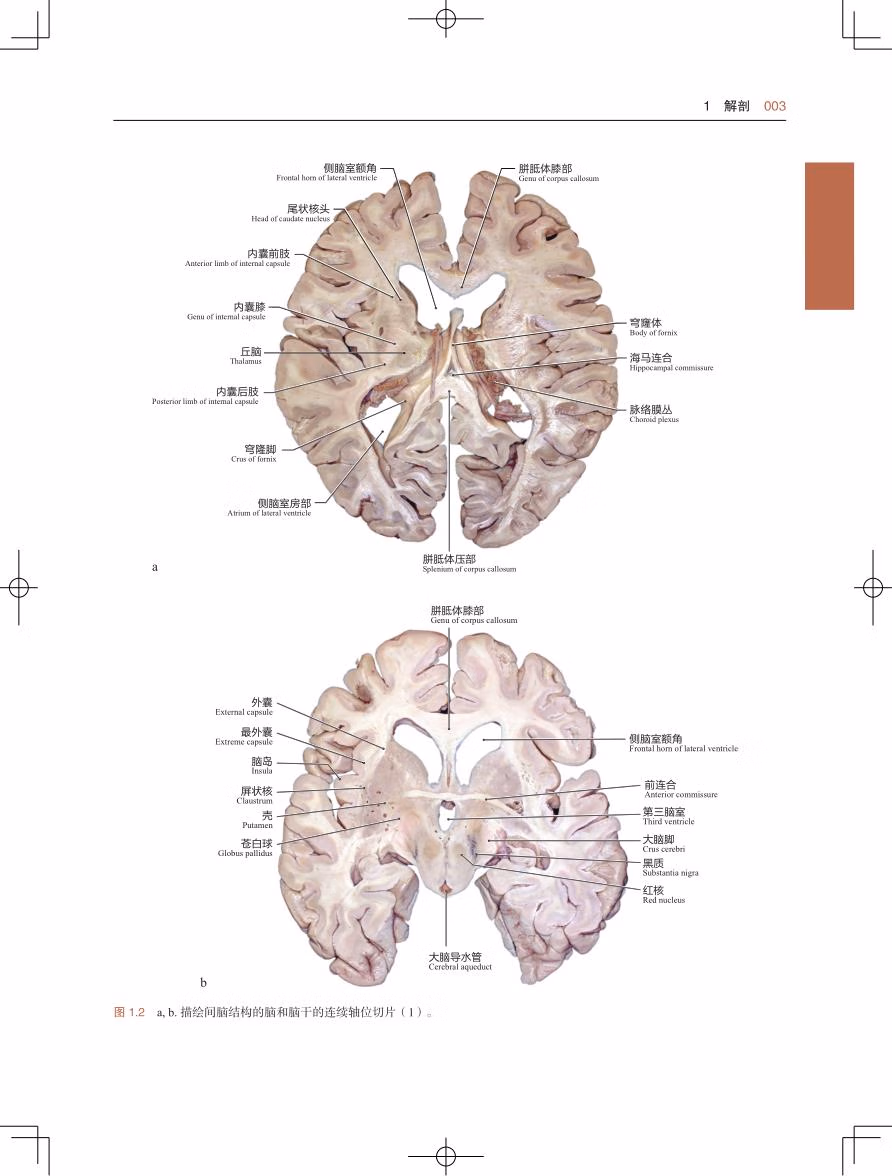

本书为国际神经外科 专家合著的关于脑干解剖及外科手术的图谱,详细介绍了脑干的神经解剖及在脑干手术中相对安全的入路,总结了脑干手术的原则及对脑干、丘脑、松果体等部位病损的手术入路解剖,同时列举了大量脑干手术的临床病例。本书以图为主,辅以简明扼要的文字解说,同时配合大量解剖绘图、病例影像学图片、手术图片(合计1 700 余幅)及视频(51 部)和动画(7 个),使读者能更好地掌握脑干手术的操作技巧。本书适合国内各级神经外科及相关科室临床医生阅读。